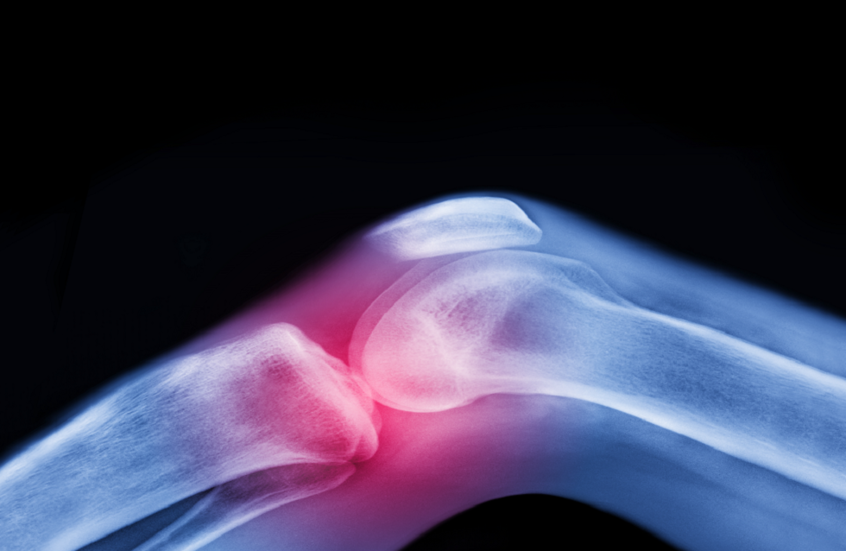

العلاج الأقوى لآلام المفاصل قبل اللجوء إلى الأدوية والجراحة

سرايا - تعتبر آلام المفاصل وتيبّس الركبتين وأوجاع الوركين من الشكاوى الشائعة بين كبار السن، وغالبا ما يُقبل بها كجزء طبيعي من أعراض الشيخوخة.

ولا يعتبر الفصال العظمي مجرد تآكل ميكانيكي للمفصل، بل مرضاً يؤثر على جميع مكوناته: السائل الزلالي والغضروف والعظم والأربطة والعضلات المحيطة، وحتى الأعصاب التي تدعم الحركة. وتستهدف الحركة المنتظمة جميع هذه العناصر، وتحافظ على صحة المفصل بكفاءة.

ويفتقر الغضروف، وهو طبقة واقية تغطي أطراف العظام، إلى إمدادات الدم المباشرة ويعتمد على الحركة للبقاء صحيا. فهو يعمل مثل الإسفنجة: ينضغط عند الحركة، فيخرج السوائل ويعيد امتصاص المغذيات، ما يحافظ على مرونة المفصل وصحته.